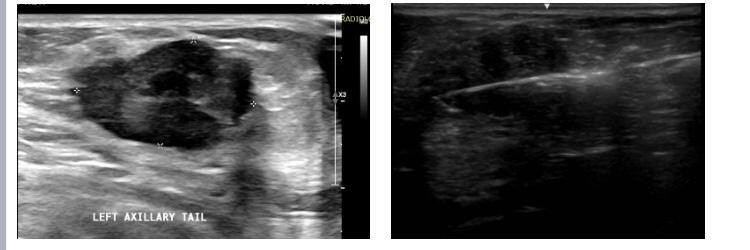

Mammogram Left MLO view shows a circumscribed high-density round to oval lesion in the upper quadrant near the axillary tail. Another partially visible high-density lesion is seen in the lower inner quadrant posterior third of the breast ( retroglandular zone) near the chest wall. Corroborative USG of the upper outer quadrant lesion revealed a hypoechoic round to oval lesion with microlobulated margins while the lower inner quadrant lesion revealed an anechoic collection with fine internal echoes reaching up to the chest wall with areas of bone erosion of the sternum. CT was done to see the extent of collection and other lesions which showed a hypodense collection in the chest wall near the sternum with areas of bone erosion and a hypodense round to oval lesion near the axillary tail. PET CT was done for academic purposes which showed uptake from the chest wall lesion near the sternum with no uptake in the hypodense collection. Biopsy was done from both the upper outer quadrant and chest wall lesion.